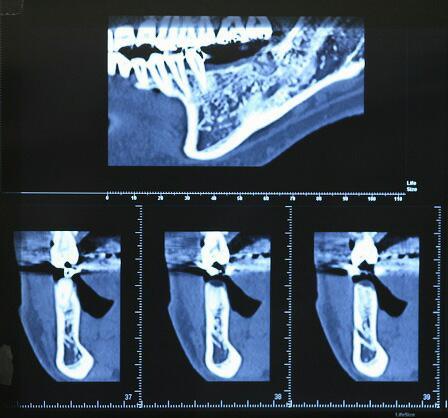

埋入手術当日

インプラントの埋入手術当日のエックス線写真です。手前の骨の密度が上がらないので少し 埋入位置を後方へ設定